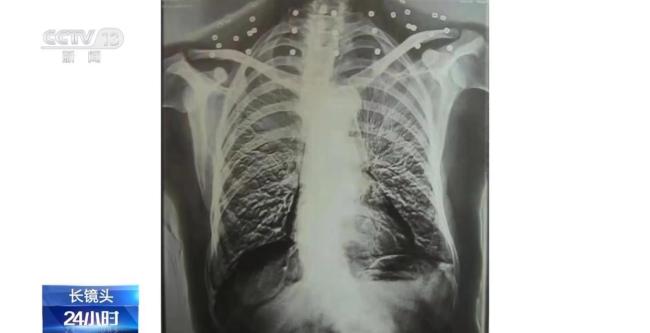

这张CT照片是82岁的吴以先老人的。当初拍片时,医生提醒他要把项链取下来再做CT。吴以先却说他从未戴过项链,怀疑那是弹片。这段对话引出了一段不平凡的往事。

二十年前,吴以先在CT检查中发现颈部有许多弹片。医生误以为是项链,提醒他取下。吴以先解释自己从未戴过项链,并推测可能是弹片。这些弹片共有33颗,成为了他摘不下的“项链”。